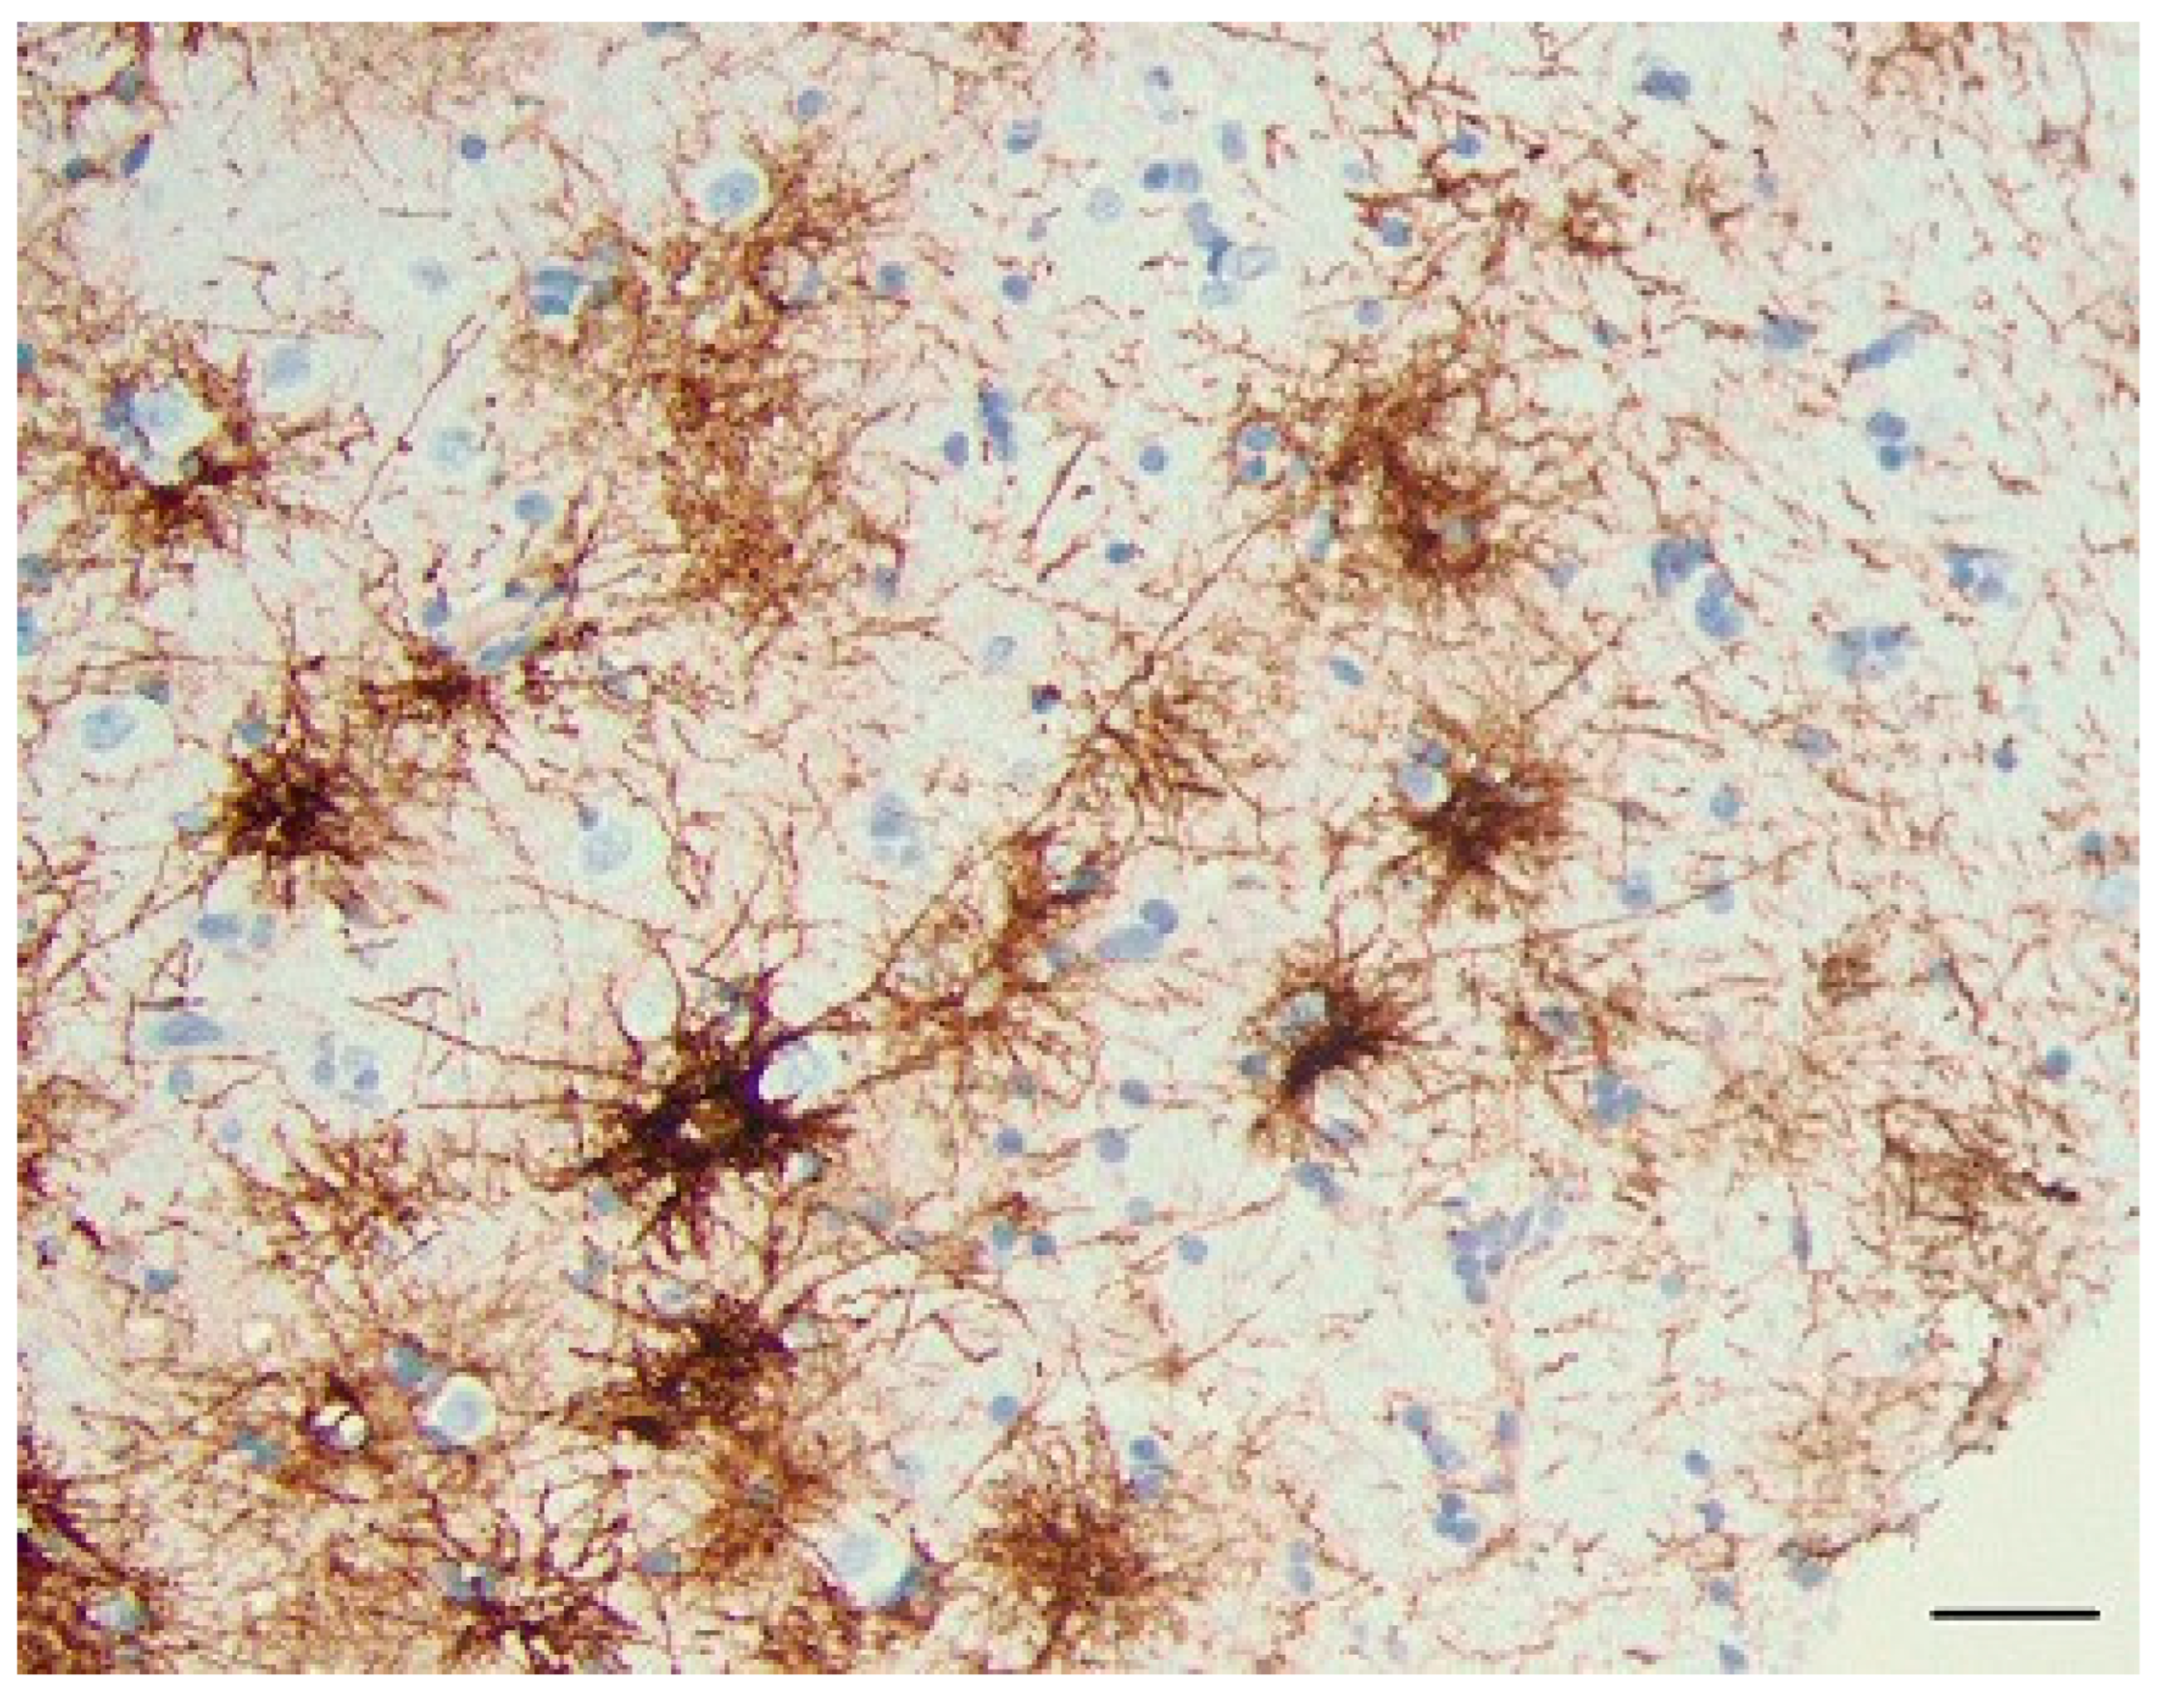

CD44+ Astrocytes in Epilepsy

Because of the reports of CD44 increase in epilepsy[14,15] and in tuberous sclerosis, which is often accompanied by seizures [13,16], we examined a group of neurosurgical specimens removed from patients with temporal lobe epilepsy, both the hippocampi and the adjacent temporal isocortex for CD44+ astrocytes. The hippocampi showed an in- crease in CD44 immunostaining in all sectors (Figure 11, and compare with Figure 4). CD44 staining of all 4 resections that contained hippocampus revealed that neurons of the pyramidal cell layer were surrounded by CD44+ processes, a morphology not present in the normal brain (Figure 11). The temporal isocortex showed a variety of increased CD44 in cortical astrocytes (Figure 12), although more appeared severe than moderate or low. We do not have the full clinical histories of all of these patients, however, and so cannot try to correlate the extent of CD44 staining with clinical behavior. Furthermore, sam- pling is an issue, since we do not know how far away the cortical samples were taken from the hippocampus. Thus, we can conclude that in some of these individuals there has been a transformation of CD44-negative protoplasmic astrocytes to CD44+ astrocytes. Inter- estingly, some of the CD44+ cortical astrocytes had extended long processes (Figure 13), an abnormal morphology for protoplasmic astrocytes, which do not extend such pro- cesses.

Figure 12. Temporal isocortex in individuals with temporal lobe epilepsy. In some resections, many astrocytes have be- come CD44+ (A). In others, fewer are CD44+ (B, C). The pial surface of the cortex is at the top. Scale bars: A, B, C 250 mm.

Figure 13. A higher magnification of CD44+ astrocytes in the temporal isocortex reveals that many of them have extended long processes, an abnormal morphology for protoplasmic astrocytes. Scale bar: A 20 mm.